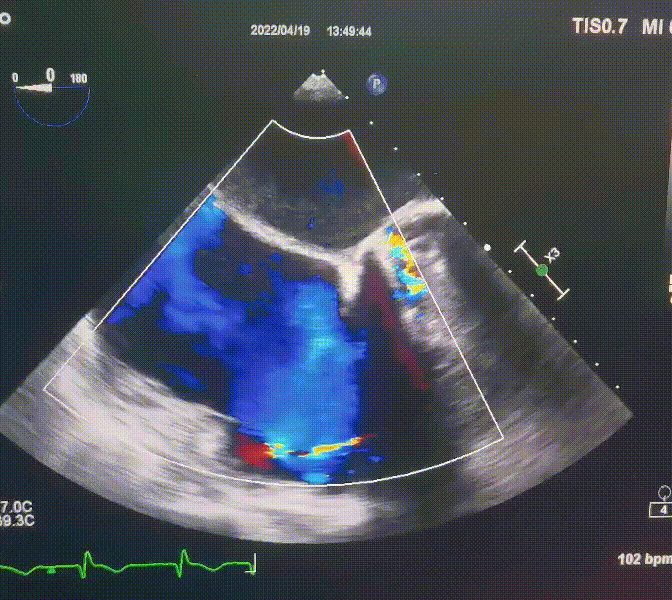

術前超聲提示:

1.右心、左房明顯增大;

2.二尖瓣人工機械瓣功能正常,無瓣周漏;

3.三尖瓣環(huán)巨大擴張,收縮期瓣葉對合不攏,收縮期三尖瓣房側見大量反流信號,反流面積15-20cm²,TRVmax:240cm/s,跨瓣壓差:23 mmHg。

圖1.術前超聲